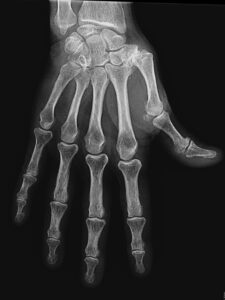

Elle correspond à l’arthrose de la base du pouce, destruction progressive des cartilages de l’articulation entre le trapèze et le premier métacarpien. Cette arthrose peut également toucher d’autres articulations autour du trapèze. Elle est très fréquente, touchant surtout la femme, et débute le plus souvent vers l’âge de 50 ans.

Elle peut être très bien tolérée malgré l’importance des signes radiologiques et des déformations du pouce, ou devenir très gênante dans la vie quotidienne entraînant des douleurs, une limitation de la mobilité de la base du pouce et une diminution de la force de serrage de la main.

Les facteurs prédisposants à cette affection sont nombreux : dégénératifs comme pour toutes les arthroses, mécaniques (mouvements répétés du pouce), héréditaires et familiaux, parfois après un traumatisme. Au fur et à mesure de son évolution qui se fait lentement sur des années, la rhizarthrose entraîne un enraidissement progressif du pouce qui gène pour attraper les gros objets, entraîne une perte de force et parfois une déformation inesthétique appelée à pouce en Z. La maladie peut également entraîner une déformation de l’articulation du milieu du pouce (la métacarpophalangienne) qui peut perdre sa flexion et se déforme parfois.